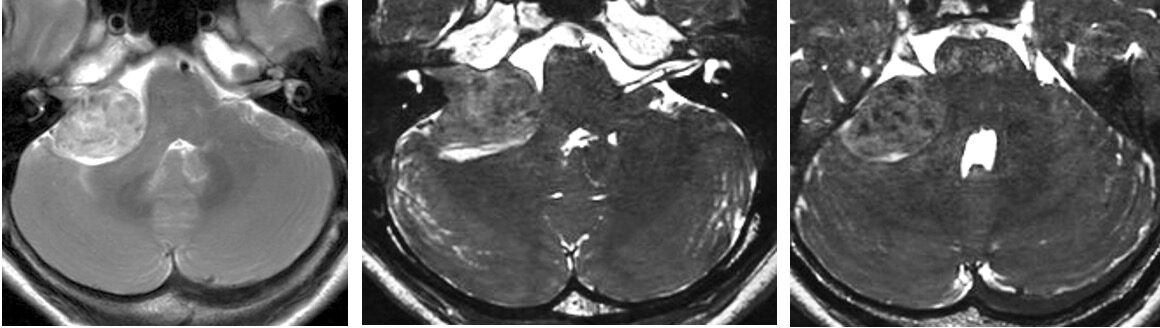

55歳女性、右聴神経腫瘍の手術を行いました。腫瘍は肉眼的に全摘出され、顔面神経麻痺は出ませんでした。 2025 12/05 聴神経・腫瘍 2025年11月12日2025年12月5日ScreenshotScreenshotScreenshotScreenshotScreenshot 聴神経・腫瘍 よかったらシェアしてね! URLをコピーしました! URLをコピーしました! 250808福井大学松岡キャンパス オープンキャンパスを開催しました。多くの高校生が参加してくださり、大盛況でした 28歳女性 ラトケ嚢胞の手術を行いました。術後一過性の尿崩症が発生ししたが、腫瘍は全摘出され視野狭窄が改善しました この記事を書いた人 kikuta 関連記事 2604月、59歳女性の左海綿静脈洞内髄膜腫(複視)に対して左内頸動脈のための左STA-MCAバイパスを行いました。 2026年4月11日 260331 60歳男性 頭蓋咽頭腫を開頭で摘出しました。 2026年4月3日 260324 78歳男性 大型下垂体腺腫を外視鏡+内視鏡の複合手術を行いました。 2026年3月26日 2026年3月 4歳女児の第四脳室腫瘍(小脳腫瘍)を手術しました。 2026年3月22日 2026年2月 74歳女性右聴神経腫瘍の手術を行いました。 2026年3月21日 260221土 令和7年度芝蘭会福井支部総会が開催されました 2026年3月21日 2026年1月 71歳女性の頭蓋咽頭種を内視鏡で摘出しました。 2026年3月1日 37歳女性 下垂体線腫を内視鏡手術しました。両耳側の視野欠損が回復しました。 2025年12月27日